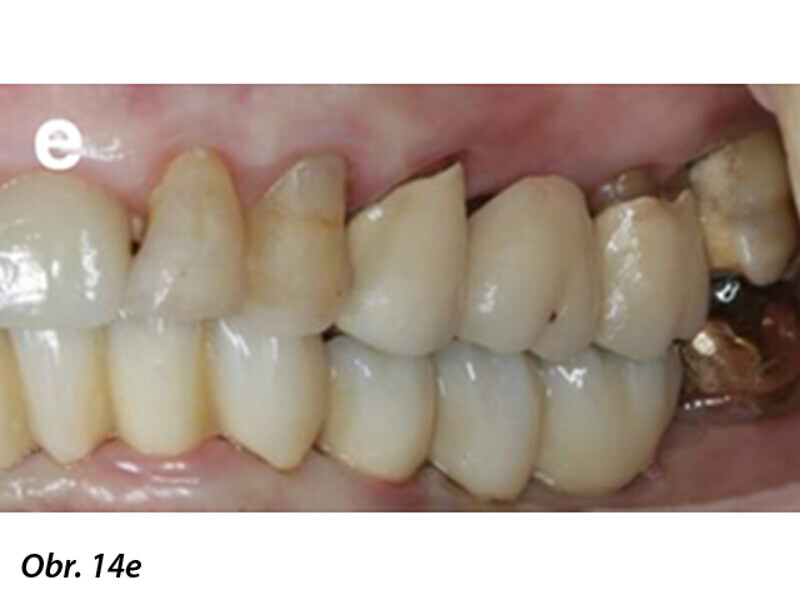

Počítačem asistované, šablonou se řídící okamžité zavedení a zatížení implantátu v dolní čelisti